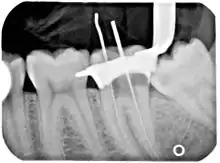

Poor-quality root filling

Another common complication of root canal therapy is when the entire length of the root canal is not completely cleaned out and filled (obturated) with root canal filling material (usually gutta percha). On the other hand, the root canal filling material may be extruded from the apex leading to other complications. The X-ray in the right margin shows two adjacent teeth that had received bad root canal therapy. The root canal filling material (3, 4, and 10) does not extend to the end of the tooth roots (5, 6 and 11). The dark circles at the bottom of the tooth roots (7 and 8) indicated infection in the surrounding bone. Recommended treatment is either to redo the root canal therapy or extract the tooth and place dental implants. Poor quality filling material or sealant may also cause root canal treatment to fail.[46]